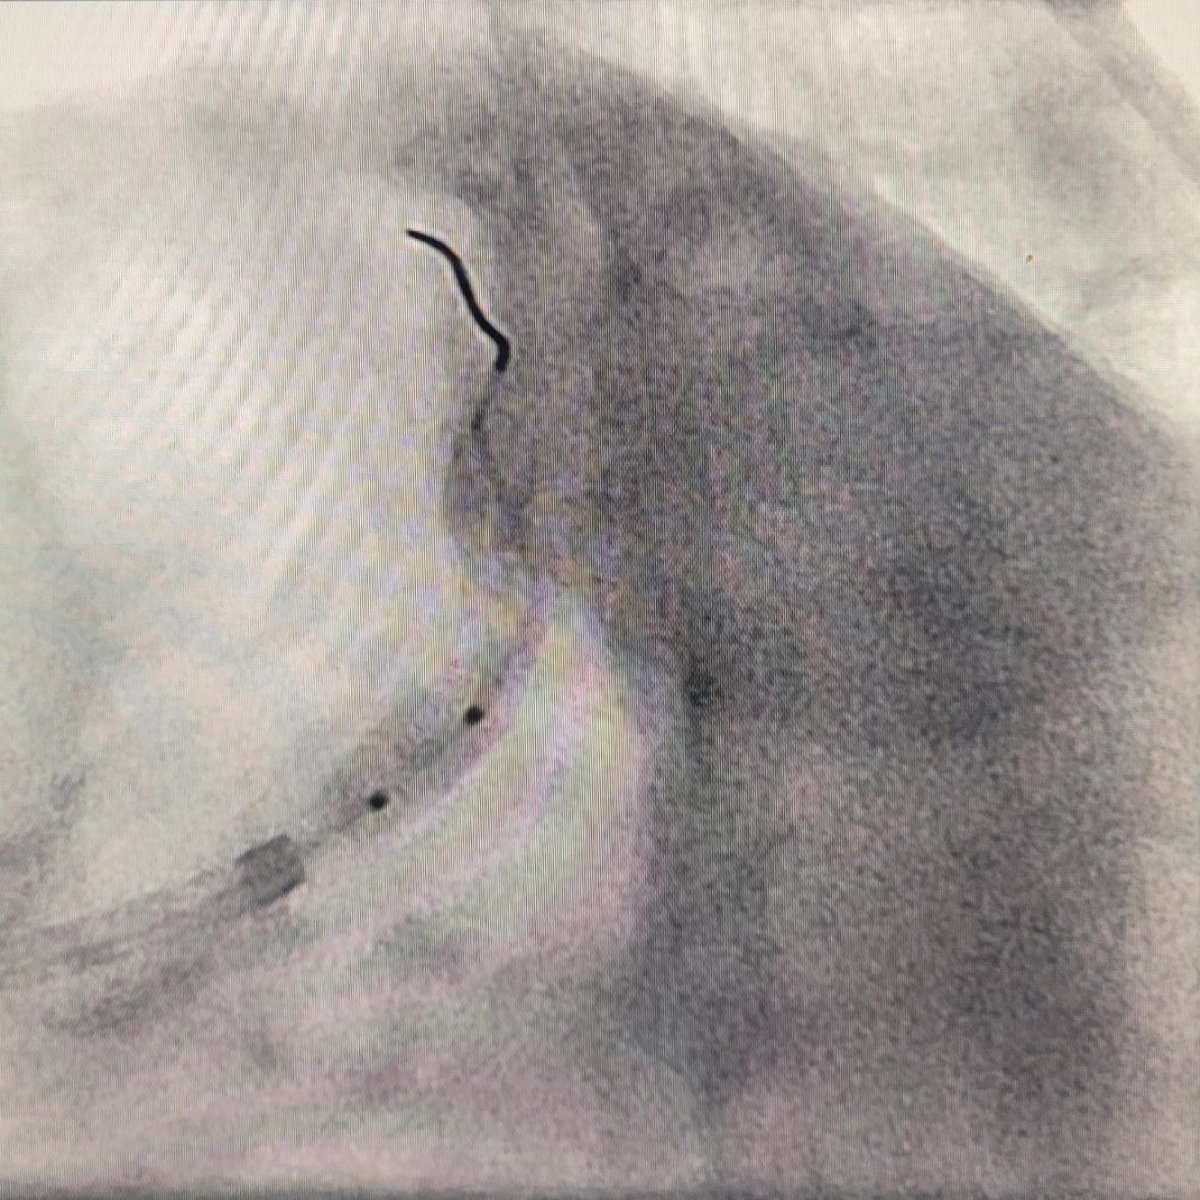

🙍🏻 ♂️ Enfermedad arterial coronaria multivasos. 3 lesiones en bifurcación incluyendo el tronco de la coronaria izquierda #leftmain. Se realiza intervención coronaria percutánea con una revascularización completa. #interventionalcardiology #cathlab #cardiologia #PCI #EACMV #IHD